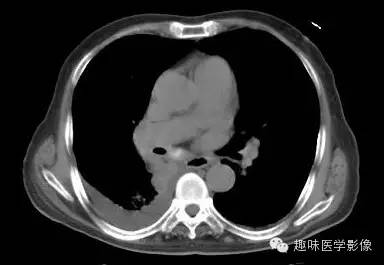

【病例】肺脓肿1例CT影像特点

男,71岁,发热待查。

双肺多发无壁低密度区,以右肺下叶底部为主。右肺下叶见大片不规则实变阴影伴多发空洞影,实变肺组织内见支气管气象,右肺下叶支气管局部显示不清。纵隔内见淋巴结。右侧胸腔内见积液影,邻近胸膜肥厚。主动脉、冠状动脉钙化。

右肺下叶肺脓肿、肺炎伴胸腔积液,肺气肿、肺大泡。

右胸廓变小,心影右移;右肺下叶多房性空洞,空洞内未见明显液平面,右下肺病变应该是下叶阻塞性肺炎,实变肺组织内见支气管气像,邻近胸膜增厚,并合并胸腔积液,支持肺脓肿。